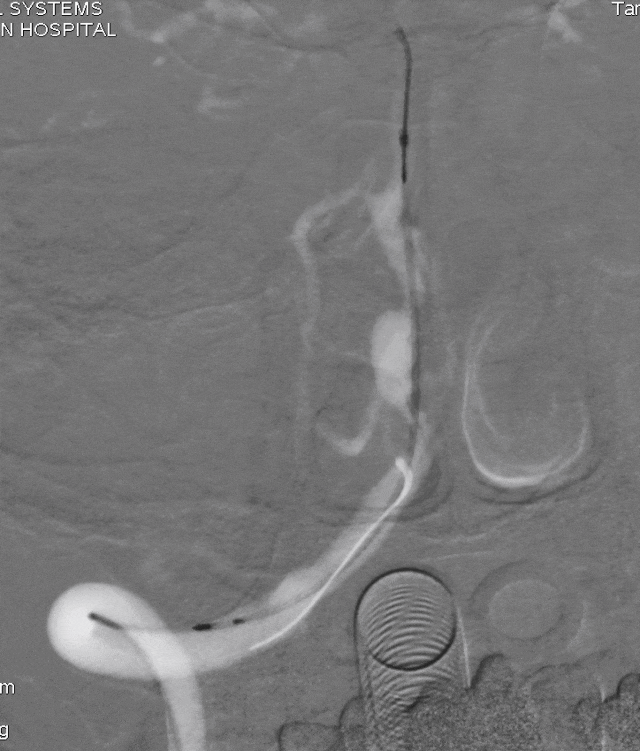

银蛇DA到位

Roadmap

通桥白驹®球囊(2.5*10),先远后近扩张。

球扩后,狭窄改善。

Marksman到位。

逐步释放Pipeline(3.00*30)。

支架完全释放,微导丝“按摩”支架。